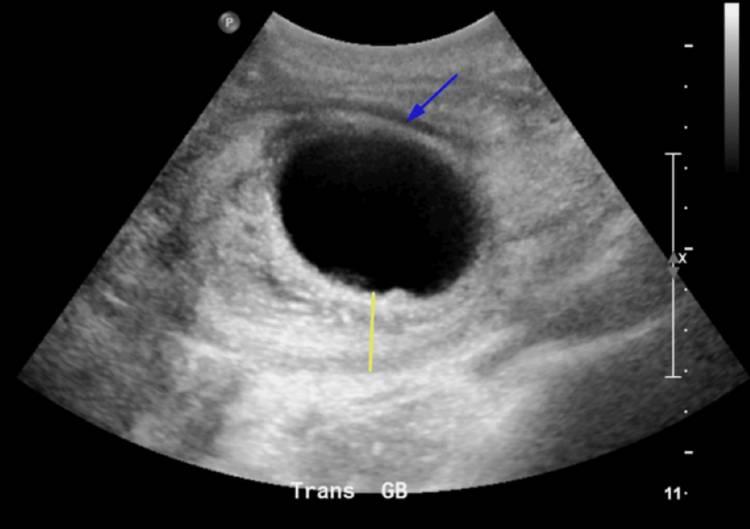

图2 胆囊横断面超声显示胆囊壁增厚和胆囊周围积液

胆囊横断面超声显示胆囊明显增大,壁增厚(黄线),并注意到胆囊周围积液(蓝色箭头),与出血性胆囊炎一致。